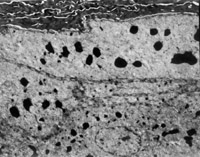

伤后12h急诊入院,检查双下肢为浅Ⅲ度烧伤。创面表皮已坏死剥脱,真皮层变性坏死呈蜡黄色和蜡白色相间(图5-3-1)。取局部组织做病理切片检查,显示上皮组织全层坏死,真皮层胶原纤维变性,结构紊乱,微循环瘀滞(图5-3-2)。

5-3-2 上皮组织全层坏死,胶原纤维变性,微循环瘀滞 HE×20